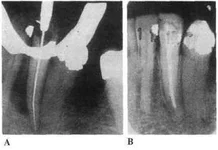

Видимый очаг разрежения костной ткани - типичной эндодонтической этиологии. Убрав причину - всё зарастёт очень быстро.

Причина многих из Ваших карманов - инфекция, находящаяся в корневых каналах. Если её оттуда убрать - будет положительная динамика.